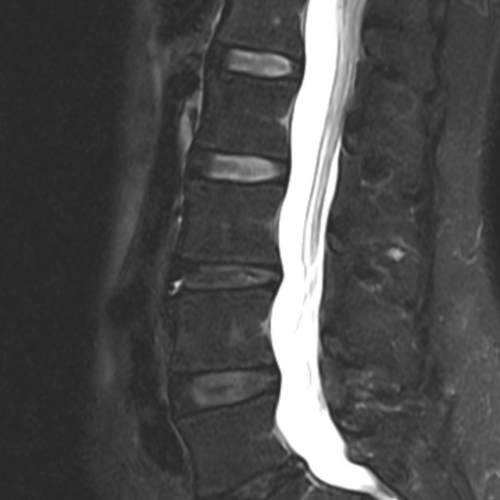

Cet examen est réalisé pour analyser les différentes structures anatomiques du rachis lombaire : disque, articulaire postérieure, sac dural, cône terminal, nerf L4 L5 S1, articulation sacro-iliaque.

Cette examen permets de diagnostiquer:

- les hernies discales

- les conflits disco-radiculaires

- les sacroiliites

- un canal lombaire rétréci

- les lyses isthmiques

- l’arthrose articulaire postérieure

- les rétrécissements de foramens

- les tassements vertébraux

- les enthésites